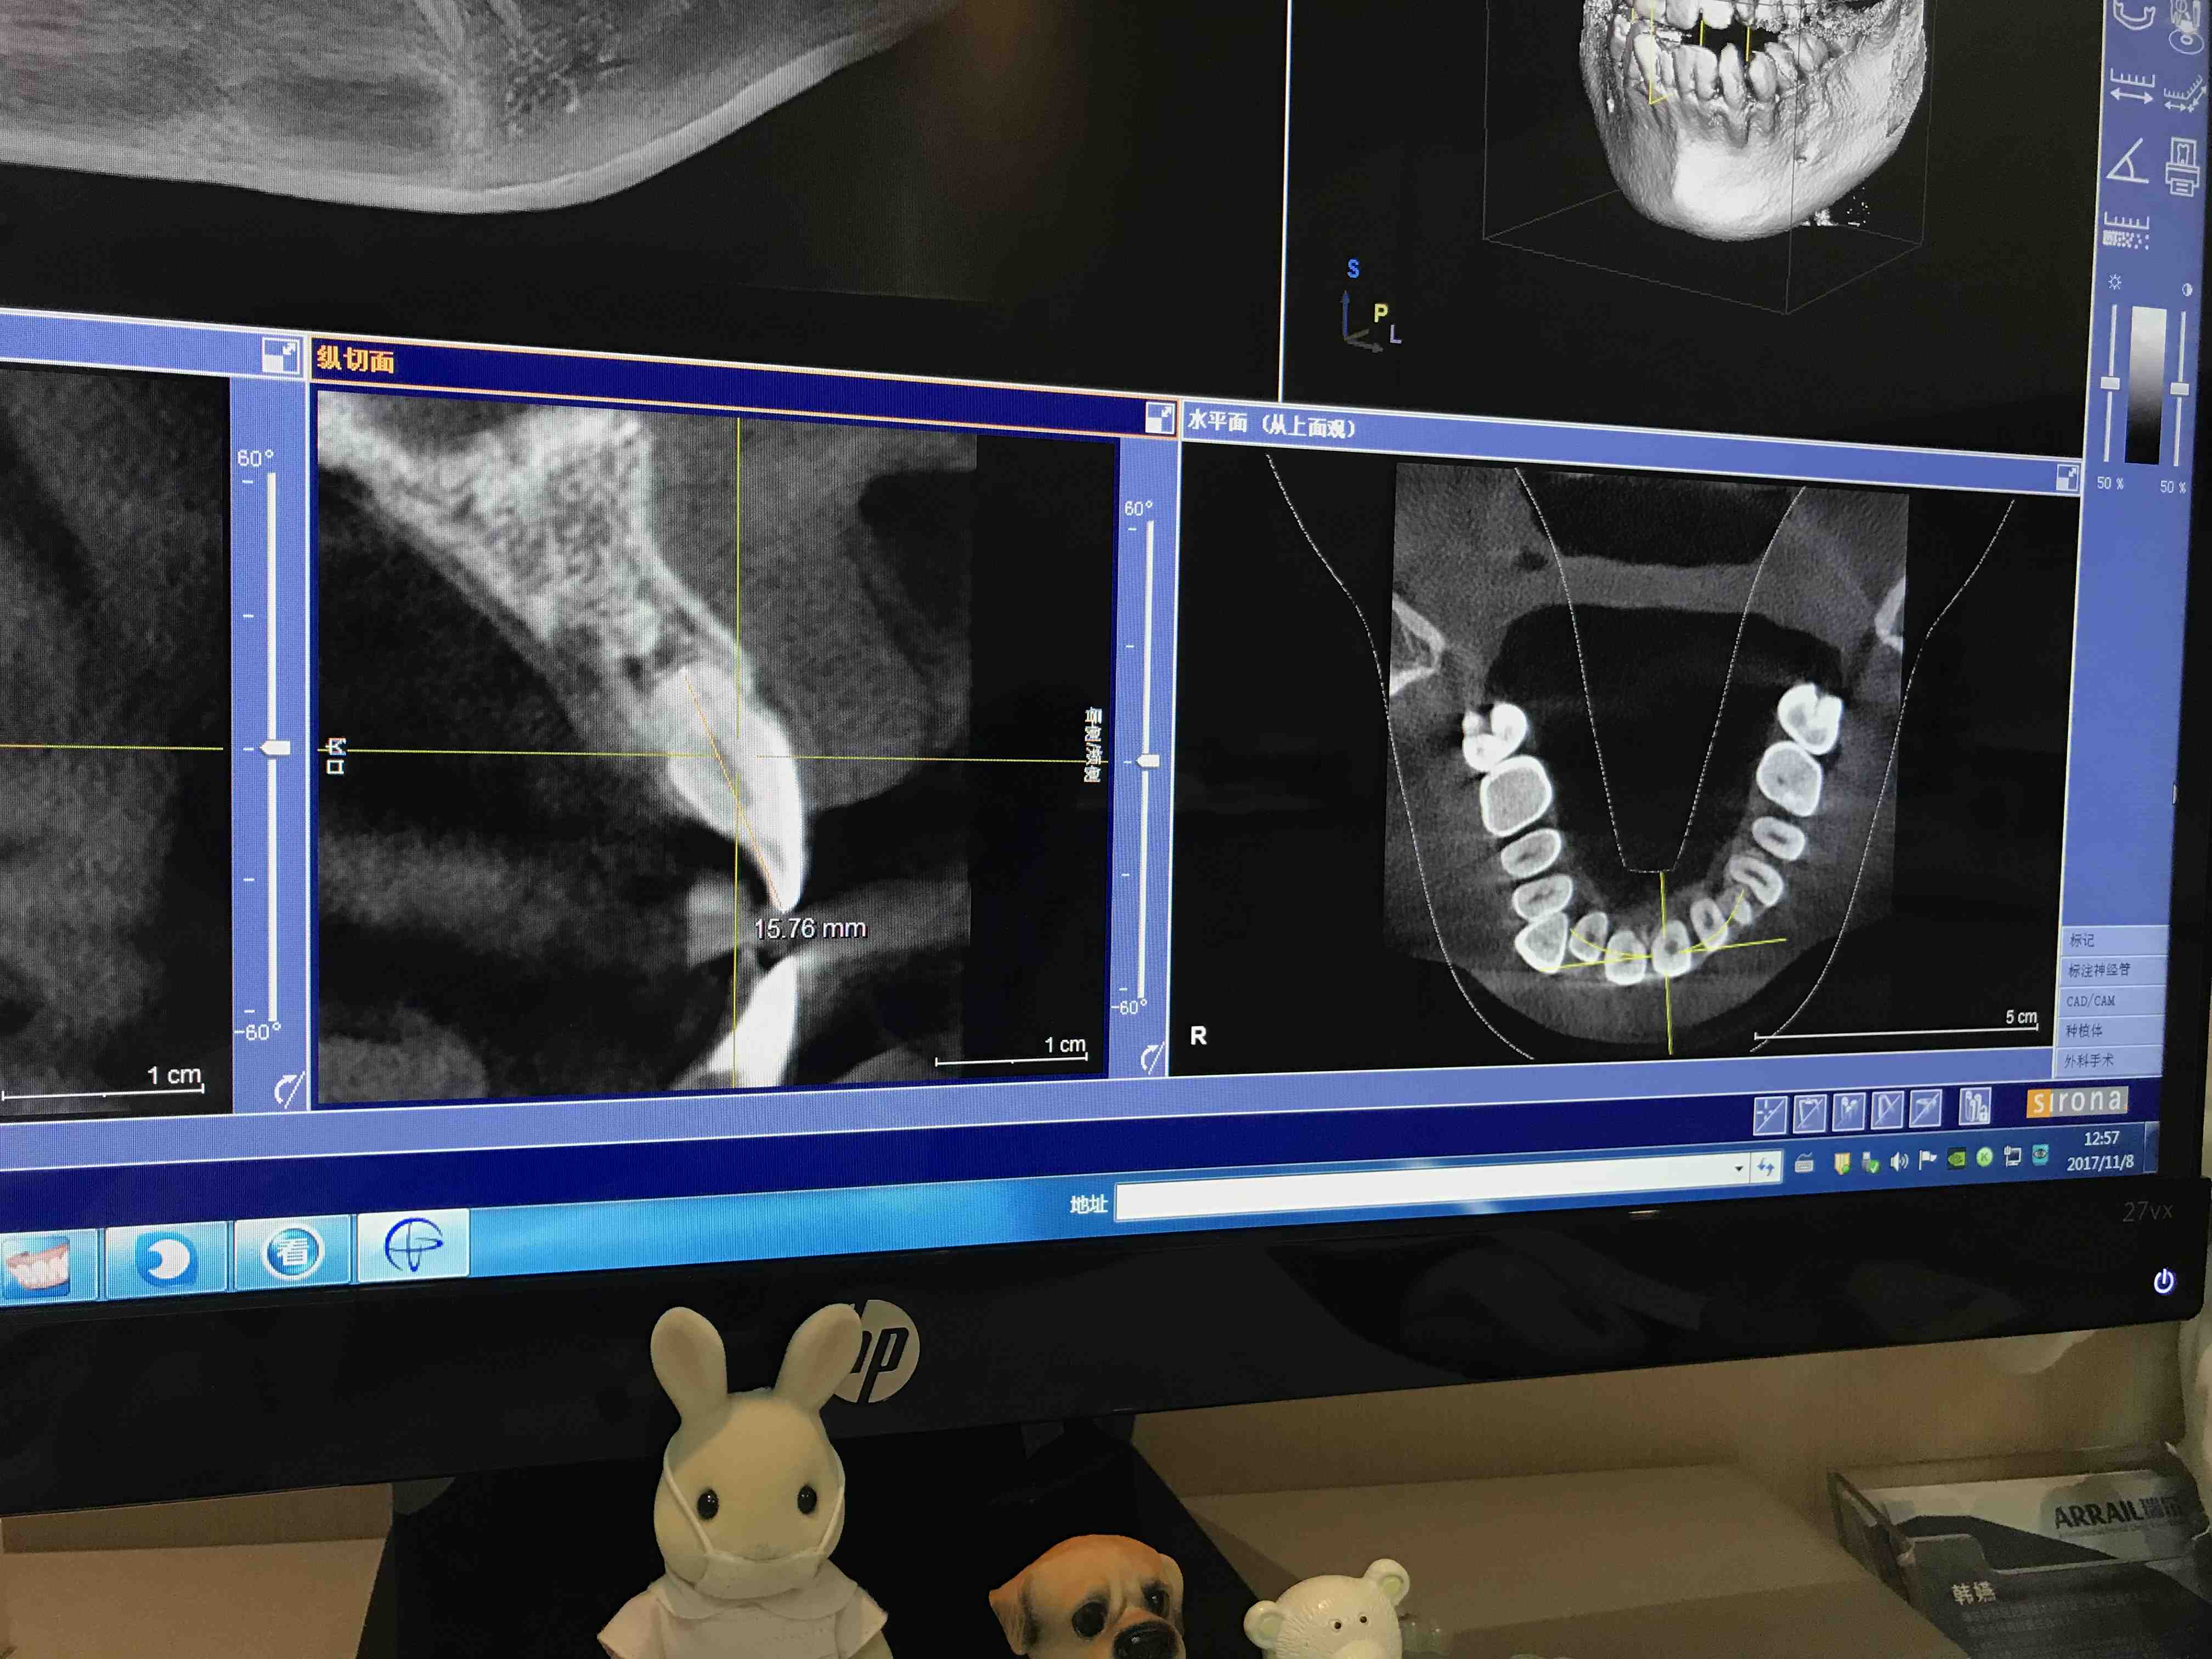

#诊间日记#最近来咨询的案例都很辣手,[捂脸]好心塞,那些简单案例都去哪儿了[流汗][流汗][流汗]这个患者10几岁的时候因为尖牙埋伏阻生,把好好的门牙牙根都给顶吸收快没了(参照图三为正常牙根长度)曾经有医生预言这2个门牙很早就会松动脱落,蓝鹅伦家门牙居然现在还蛮牢,我检查过发现真是如此,可见牙根长短并不直接影响松动度.......出于牙周风险考虑我建议患者还是不动为好吧,患者问:"如果这2个门牙以后迟早会松动脱落,那可以镶假牙吗?如果可以镶的话我还是想早点让我的牙齿变整齐,笑容变好看一点......."轮到我纠结上了,这样的患者要接吗?能接吗?